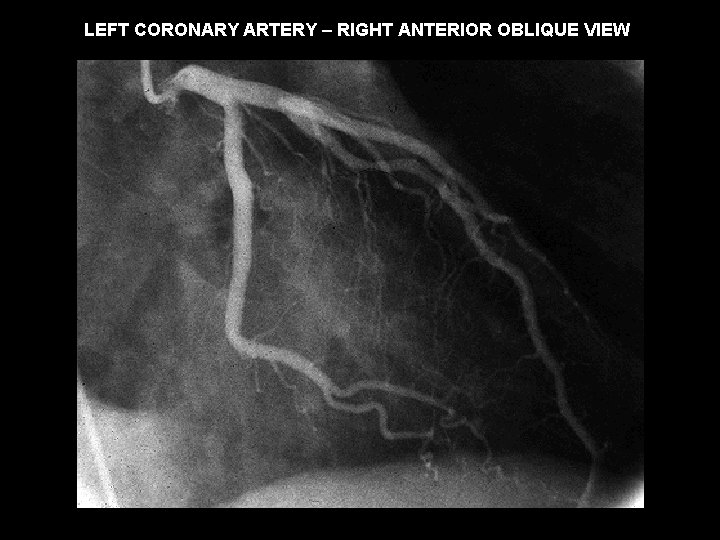

LEFT CORONARY ARTERY – RIGHT ANTERIOR OBLIQUE VIEW